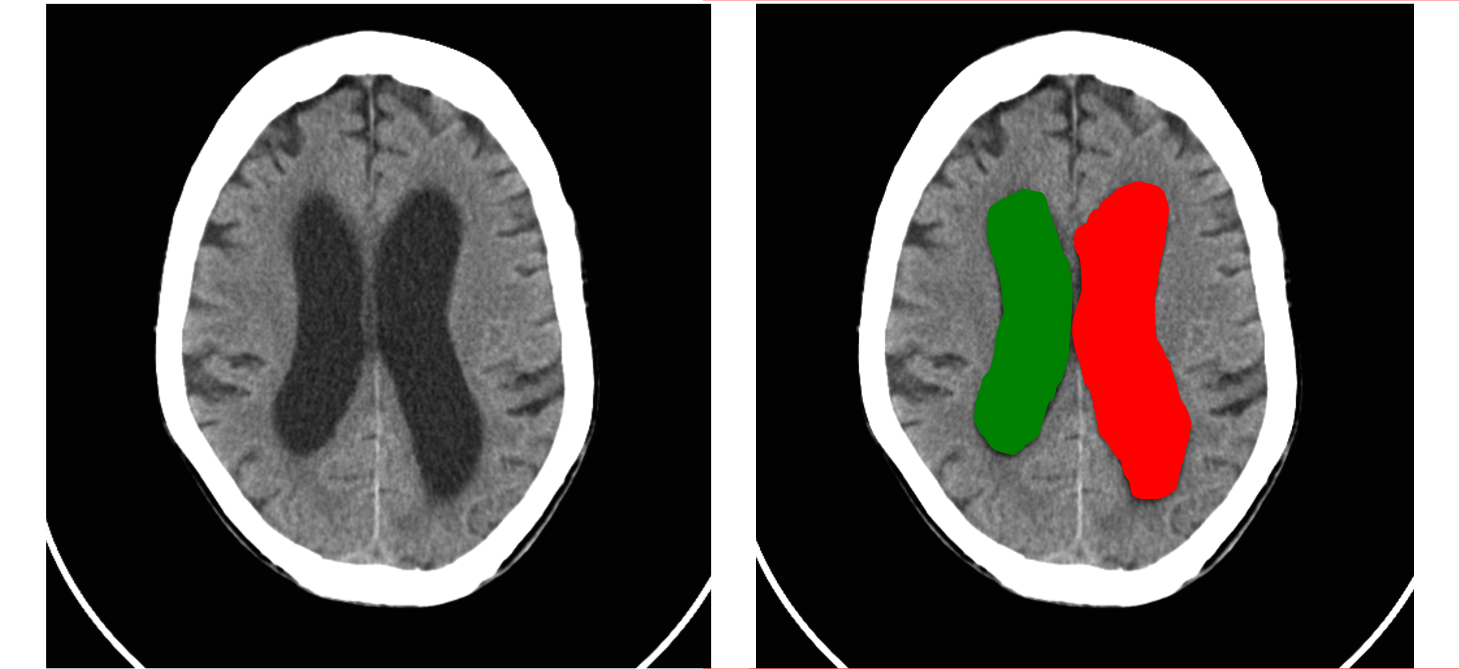

En un estudio retrospectivo de resonancia magnética de 2536 hombres jóvenes sanos de edades entre 17 y 35 años, media de 20,5 años, las variantes anatómicas normales estaban presentes en el 18,45%con la siguiente distribución: cavum vergae, 4,77%; grandes cisternas basales, 1.74%; quistes de la glándula pineal, 3.43%; espacios perivasculares ampliados, 2.56%; asimetría de los ventrículos laterales, 2.68%; lesiones de sustancia blanca aisladas, 2.6%; osificación de la hoz cerebral, 0.32%; y silla turca vacía, 0,35% (3).